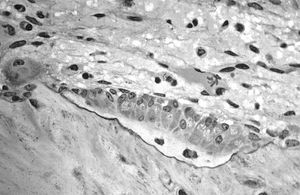

뼈의 단단한 바깥층은 '''겉질뼈'''(피질골)로 구성되어 있으며, 해면골(갯솜뼈)보다 훨씬 밀도가 높기 때문에 '''치밀골'''이라고도 한다. 겉질뼈는 뼈에 매끄럽고 흰색이며 단단한 외관을 부여하며, 성인 인간 골격 전체 뼈 질량의 80%를 차지한다.[10] 겉질뼈는 신체를 지지하고, 장기를 보호하며, 움직임을 위한 지렛대를 제공하고, 주로 칼슘을 포함한 화학 원소를 저장하고 방출하는 뼈의 주요 기능을 돕는다.겉질뼈는 각기 오스테온(하버시안 계통)이라고 하는 여러 개의 미세한 기둥으로 구성된다. 각 기둥은 골아세포(뼈모세포)와 골세포(뼈세포)가 오스테온관이라고 하는 중심 관 주위에 여러 겹으로 이루어져 있다. 수직으로 된 볼크만관은 오스테온을 서로 연결한다. 기둥은 신진대사가 활발하며, 뼈가 재흡수되고 생성됨에 따라 오스테온 내 세포의 성질과 위치가 변화한다.

겉질뼈는 바깥 표면에 골막(뼈막)으로 덮여 있고, 안쪽 표면에는 골내막(뼈속막)으로 덮여 있다. 골내막은 겉질뼈와 해면골 사이의 경계이다. 겉질뼈의 주요 해부학적 및 기능적 단위는 오스테온이다.

뼈의 전형적인 구조는 치밀질 부분에서 볼 수 있으며, 가느다란 혈관을 중심으로 하는 동심원상 단면 구조를 가진 원주(圓柱)가 단위 구조를 이룬다. 이것을 '''하버스관(管)''' 또는 '''오스테온(골단위)'''이라 한다. 뼈의 단단한 바깥층은 '''피질골'''로 구성되어 있으며, 해면골보다 밀도가 높아 '''치밀골'''이라고도 한다. 피질골은 뼈에 매끄럽고 흰색이며 단단한 외관을 부여하며, 성인 인간 골격 전체 뼈 질량의 80%를 차지한다.[10] 각기 오스테온 또는 하버시안 계통이라고 하는 여러 개의 미세한 기둥으로 구성된다. 각 기둥은 골아세포와 골세포가 오스테온관이라고 하는 중심 관 주위에 여러 겹으로 이루어져 있다. 수직으로 된 볼크만관은 오스테온을 서로 연결한다. 피질골은 바깥 표면에 골막으로 덮여 있고, 안쪽 표면에는 골내막으로 덮여 있다. 골내막은 피질골과 해면골 사이의 경계이다. 피질골의 주요 해부학적 및 기능적 단위는 오스테온이다.